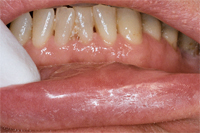

Die Abb. 1 bis 4 sollen als anschauliche Beispiele für gesunde und kranke Fundamente dienen.

Ein 31 Jahre alter Patient zeigt einen starke Zahnfleisch-Rückgang im Oberkiefer (Abb. 1 und 3) und wir beschliessen, diese Rezessionen zu behandeln.

Der Erfolg der Behandlung ist deutlich in den Abb. 2 und 4 zu sehen. Sehr augenfällig konnte die Situation um den Eckzahn im linken Oberkiefer verbessert werden (vergleiche dazu Abb. 3 vorher und Abb. 4 nachher).